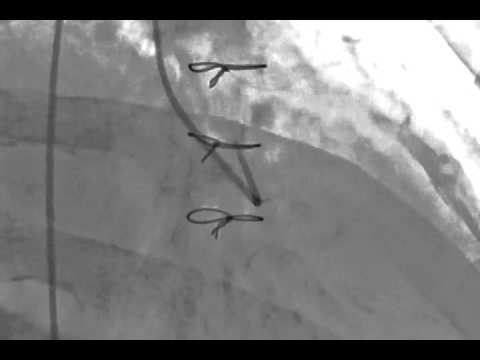

Video 7.15

Video 7.15: Engaging an occluded right coronary bypass graft with the MP catheter; LAO projection